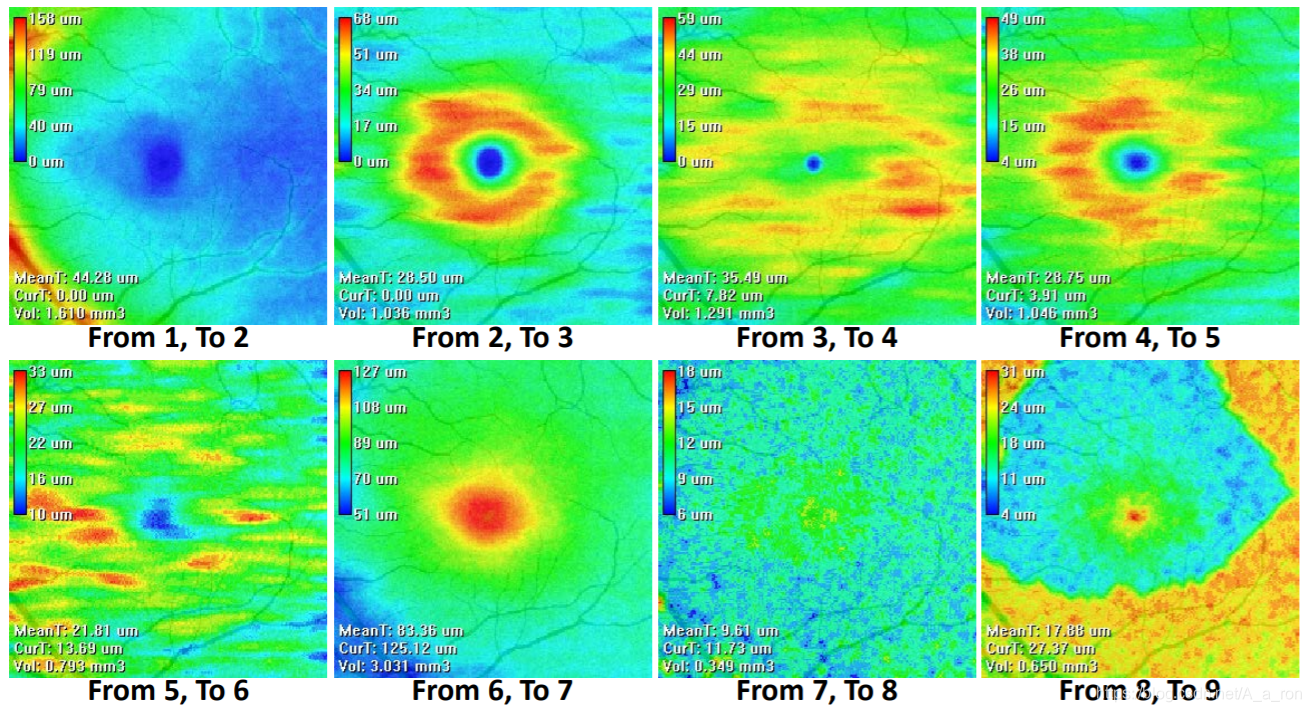

视网膜厚度分析:

ETDRS分区分析:

ReLayer: 一个免费且在线的用于眼科OCT影像分析的跨平台工具。目前的分析主要包括视网膜层次分割和厚度分析。如层次分割:

厚度分析: